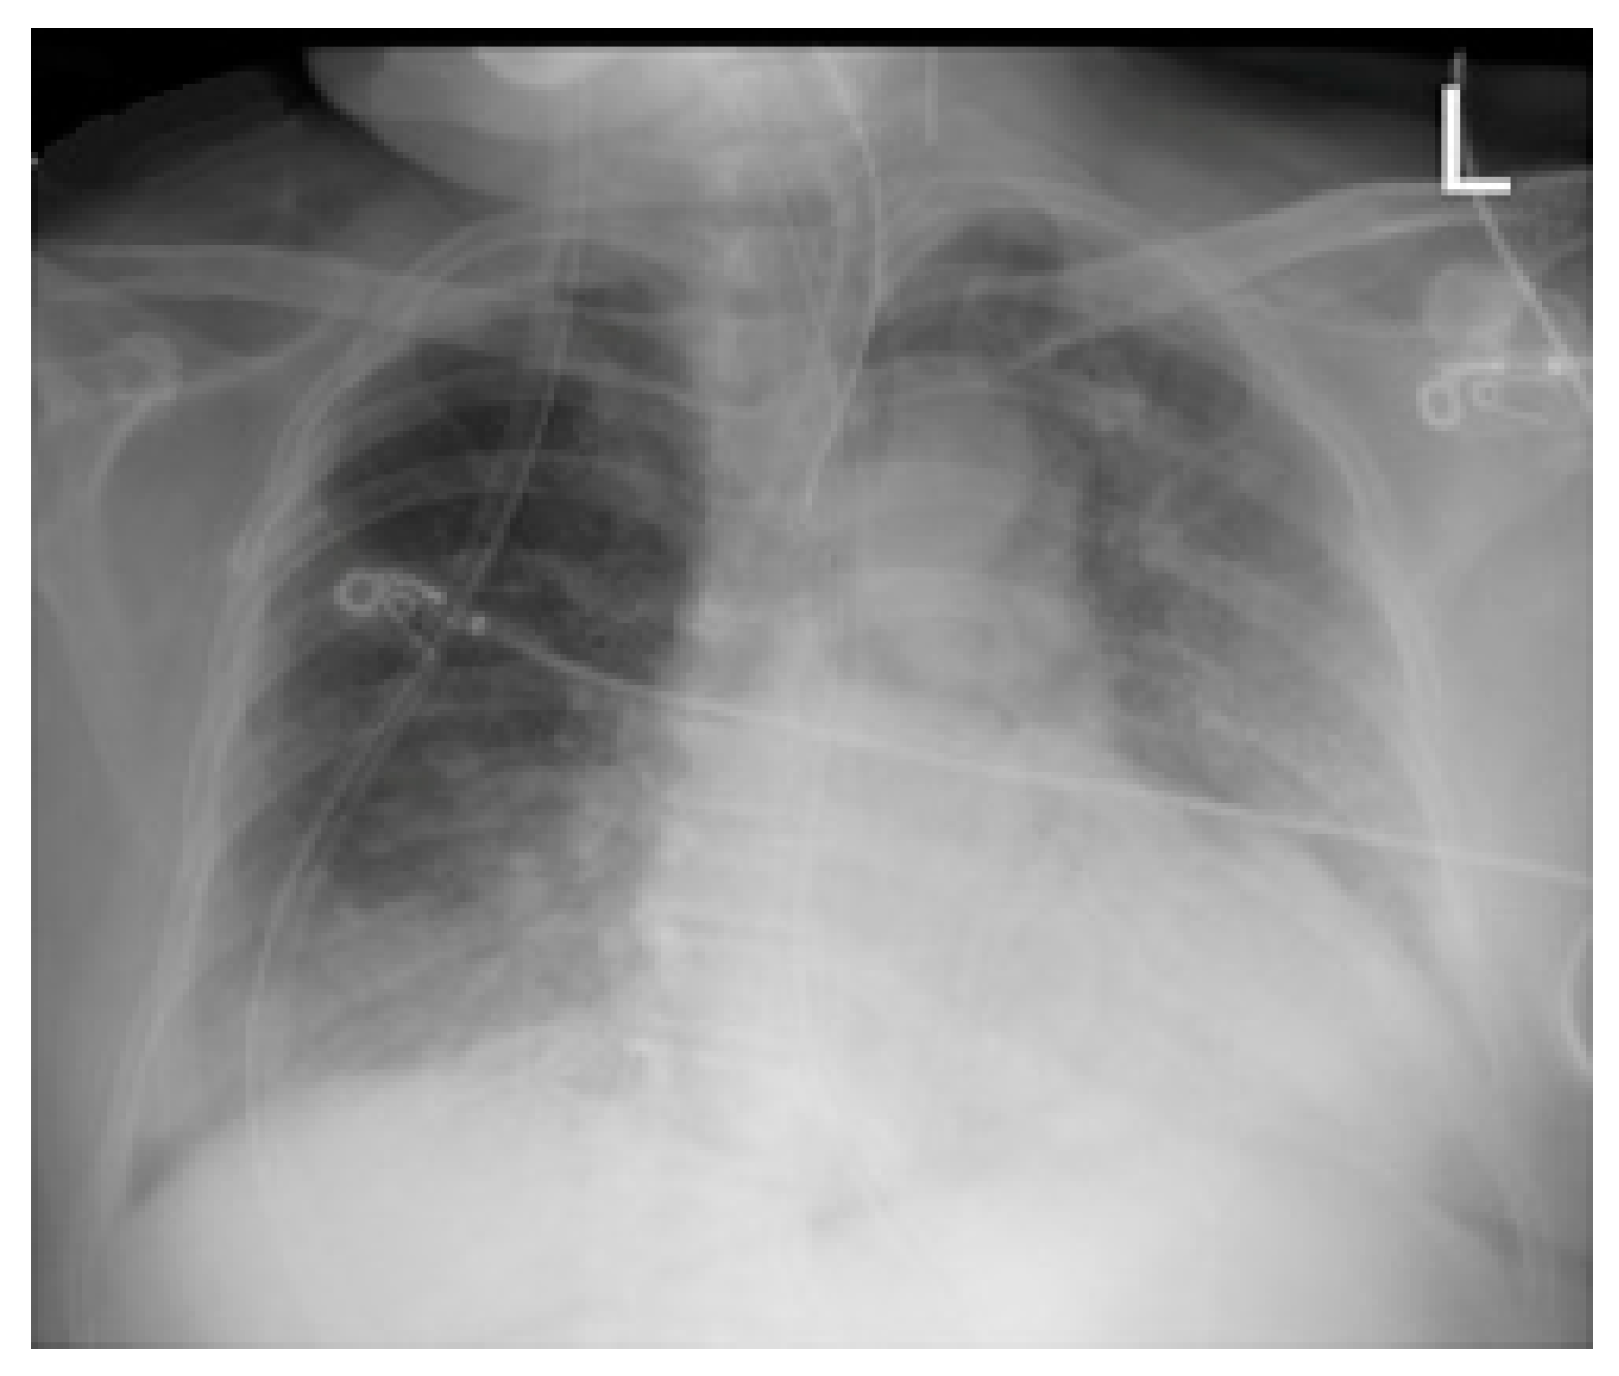

2.3. Imaging and Analysis